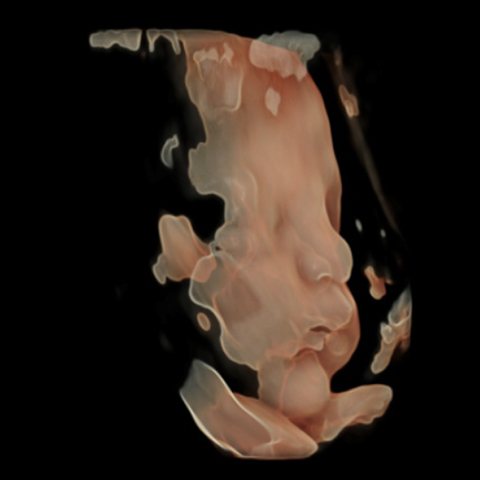

גלריה